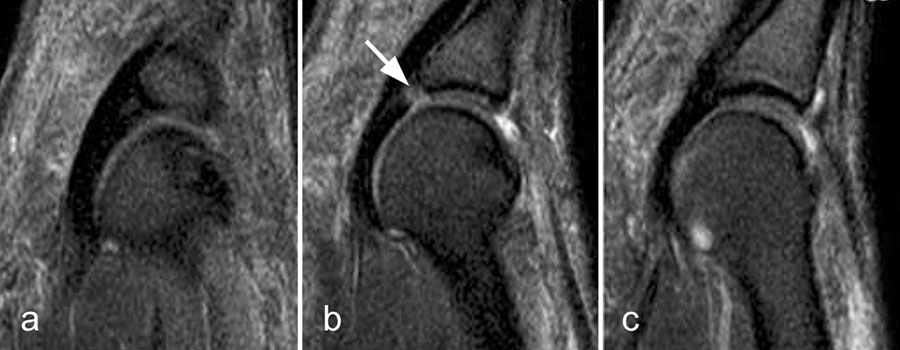

Durch seitliche Kompression des Fußes verlagern sich Morton-„Neurome“ oft weiter nach plantar in die Weichteile. Klinisch entspricht dies dem sogenannten Mulder-Zeichen 4. In der Bildgebung kann man sich den Effekt zu Nutzen machen, indem man in Bauchlage untersucht und durch die seitliche Fixierung eine entsprechende Kompression erzeugt. Die Befunde sind dann oft deutlich besser zu erkennen (Abb. 11).

Morton-„Neurome“ liegen fast immer im zweiten oder dritten Interdigitalraum. Zu beachten ist, dass Morton-„Neurome“ über lange Zeit größenkonstant sein können (Abb. 12) und kleinere Morton-„Neurome“ (unter 5 mm) sehr häufig bei asymptomatischen Gesunden beobachtet werden.

Problematisch ist die Untersuchung nach früherer Resektion, da operativ bedingte fibrotische Veränderungen häufig sind und ein Rezidiv vortäuschen können. Eine bildgebende Unterscheidung asymptomatischer von symptomatischen Befunden ist nicht immer möglich 5.